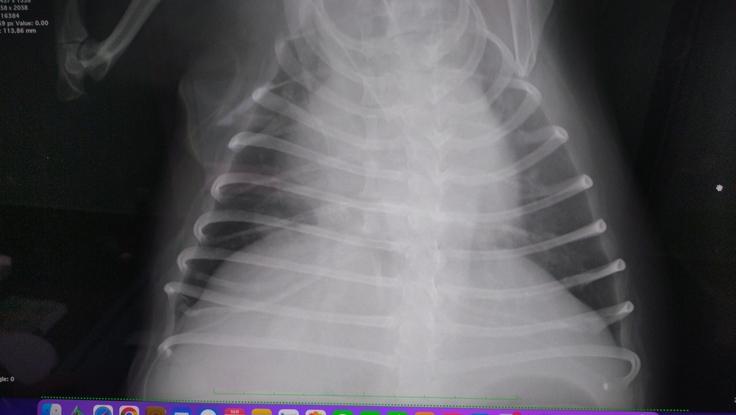

肺に転移はほぼ確定…影あり。角度によっては見えないけど、、、

肺炎はなし。